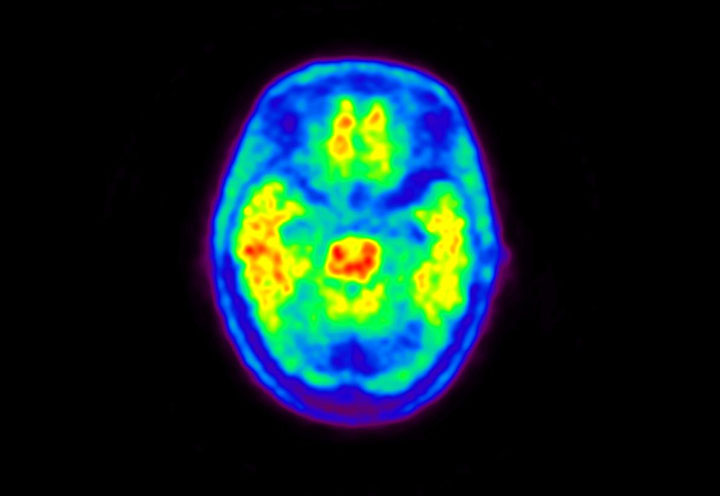

Head / Case5 : Amyloid

Courtesy : Kindai University Hospital

- Imaging protocol

- Injected dose: 4.27 MBq/kg, 18F-Flutemetamol

- Uptake time: 99 minutes

- Scan time: 20 minutes